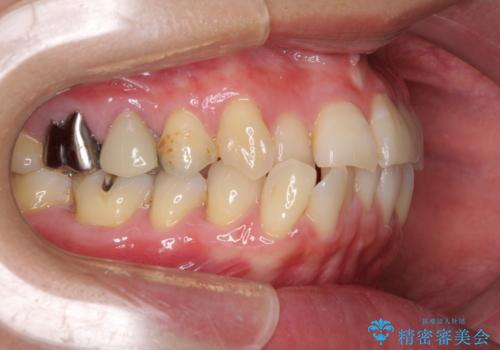

上下前歯の先端同士が接触する切端咬合であったため、上顎は歯列を拡大し、下顎はIPR(歯と歯の間を削る)により叢生を解消しながら歯列を小さくすることとしました。

治療途中に前歯に歯髄充血を思わせる痛みが認められたため、無理のない歯の移動と頻繁な経過観察を行いました。

切端咬合はスムーズに解消され、前歯の負担を軽減させることができました。